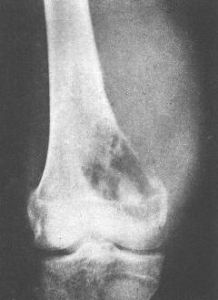

中心性軟骨肉瘤中心性軟骨肉瘤可表現為邊界模糊的溶骨,有或無皮質骨中斷,由於軟骨傾向於鈣化和骨化,腫瘤內可出現不透X線區,鈣化經常發生在軟骨小葉的周圍,無一定結構,其特徵為不規則的霧狀顆粒、結節或不透X線的環。

由於瘤壁骨嵴,腫瘤可產生泡狀或麵包屑樣外觀。如鈣化緻密,腫瘤可呈不透X線的金屬樣。如腫瘤浸潤到松質骨的髓腔而未破壞骨小梁時,鈣沉積和反應性骨增生可呈不透X線均勻一致的海綿骨樣。如腫瘤浸潤松質骨未破壞骨小梁且無鈣化時,骨內的腫瘤部分可不顯影,在這種情況下,如果不藉助骨掃描、CT和MRI,中心性軟骨肉瘤的診斷困難且晚。分化良好的中心性軟骨肉瘤鈣化多,而Ⅲ級中心性軟骨肉瘤及反分化中心性軟骨肉瘤鈣化少且粘液區多。皮質骨可以很薄,內部呈扇貝狀,在一些區域可有中斷。有時由於腫瘤膨脹緩慢,皮質骨發生增生,可顯得增厚。這種增厚的皮質骨表現相當典型,表明其已被腫瘤所浸潤。

中心性軟骨肉瘤傾向於向阻力較小的地方擴張,如骨幹的髓腔。在幾乎一半的病例中,放射影像顯示腫瘤侵犯整個長骨的1/3、1/2或更多,但在腫瘤早期,影像上可能無顯示。這個特點很重要,否則手術方案可能不恰當,切除緣可能不夠,於骨幹切除或截肢術後殘肢處腫瘤可復發,為避免發生,須在術前通過骨掃描、CT和MRI來確定腫瘤在髓腔內的範圍。

在侵襲性較強的病例中,中心性軟骨肉瘤早期即可有廣泛的皮質中斷,較大的軟組織腫塊,侵入軟組織中的瘤塊鈣化不明顯。受浸潤被頂起的骨膜可以反應性地產生薄的、稍不透X線的帶,垂直於皮質,但從不見在骨肉瘤中典型的“牙刷”影像以及Codman三角。